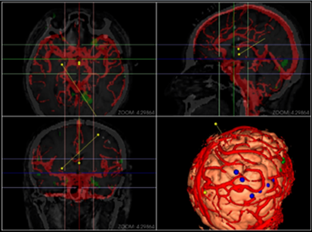

同方鼎欣專業(yè)影像產(chǎn)品群是直接面向神經(jīng)外科、骨科、血管分析等臨床科室的輔助診療、手術(shù)計劃、分析的解決方案,系統(tǒng)整合了醫(yī)療影像的導入、二維閱片、三維重建、序列配準融合、自動分割、自動計算、手術(shù)計劃等一系列功能。充分滿足了臨床科室的專業(yè)需求,提供了完整、強大、可靠、方便的工具平臺。

三維體繪制重建(VR)、三維面繪制重建(SR);

融合(Fusion)、融合結(jié)果三維重建;

3D序列血管分段及管理;

血管中心線勾畫,曲面重建(CPR);

神經(jīng)外科手術(shù)規(guī)劃模塊;

心腦血管分析模塊